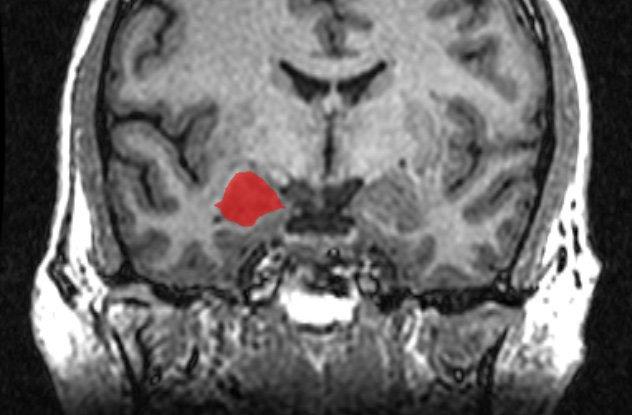

مراكز الخوف الموجود في الجمجمة والتي تتسبب لنا في الشعور بالخوف أو عدم الشعور به، توجد في الوزة الدماغية داخل الفص الصدغي من المخ ، وتمكن العلماء من التوصل لهذه الحقيقة العلمية، عندما أجروا أبحاثًا على فئران التجارب.